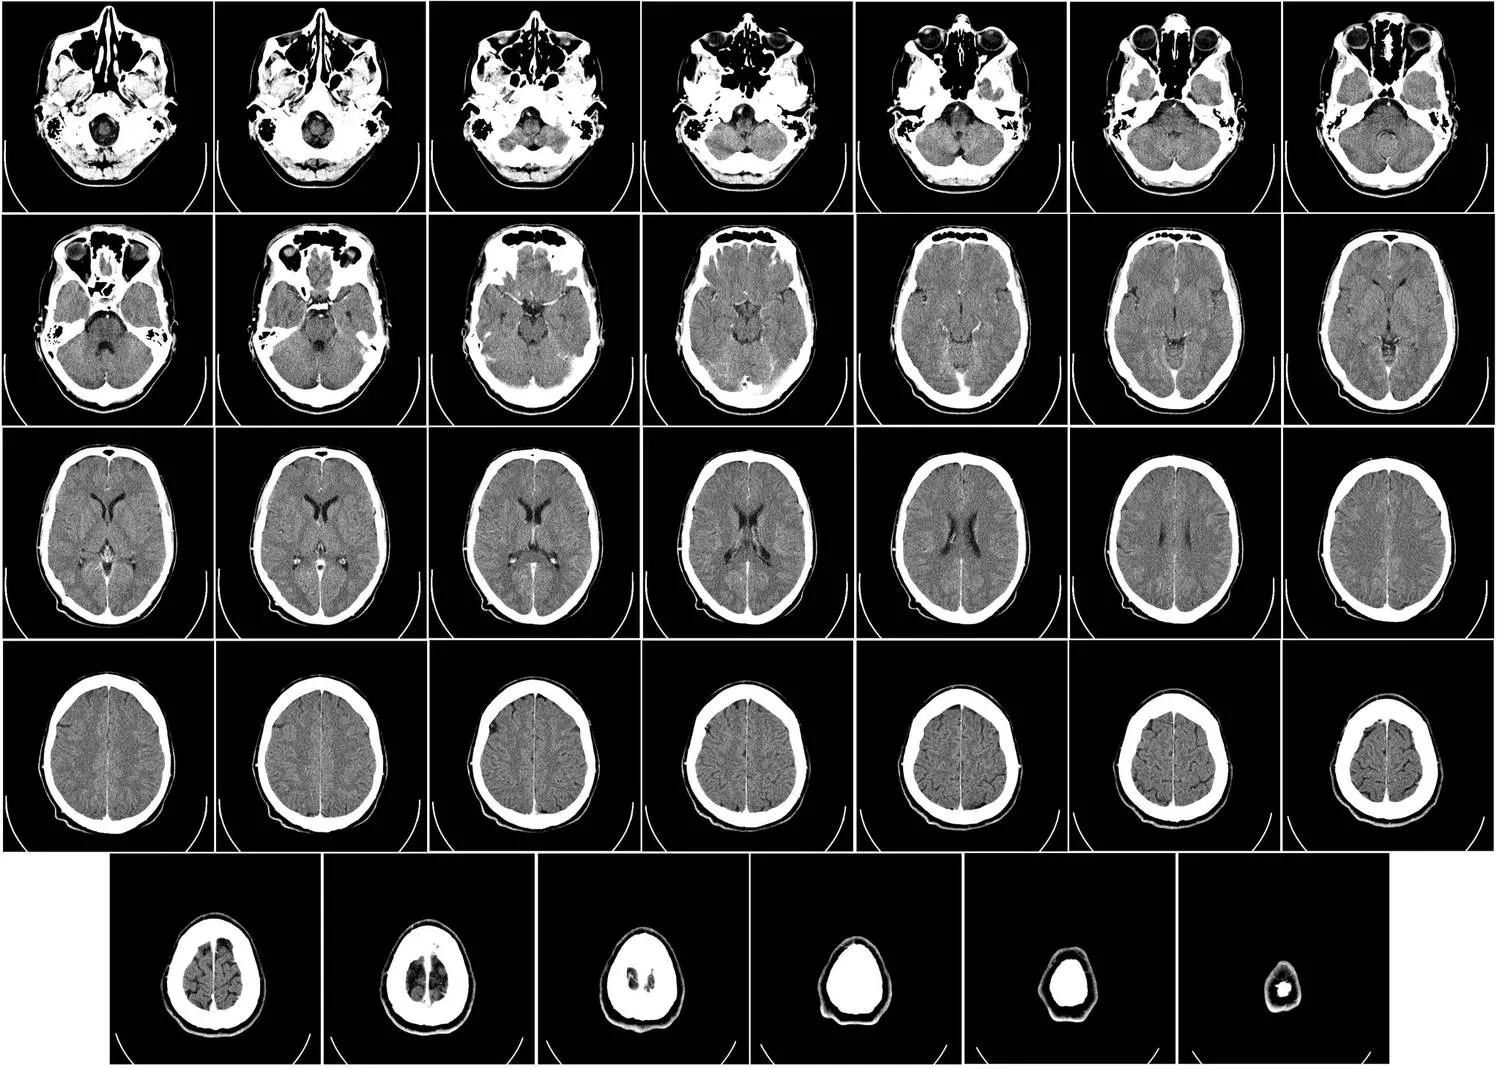

CT-felvétel az agyról

CT-felvétel az agyról (forrás: Department of Radiology, Uppsala University Hospital, Mikael Häggström; Wikimedia Commons)